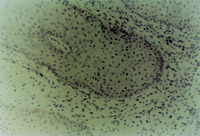

ԭλÇÐÈ¡´´Ãæ×éÖ¯²¡ÀíÇÐÆ¬¼ì²é£¬£¬ £¬£¬£¬£¬£¬£¬¼û»µËÀÉÏÆ¤×éÖ¯¼äÓдó×Ú¿ÅÁ£Ñù×éÖ¯£¬£¬ £¬£¬£¬£¬£¬£¬ÐÂÉúÉÏÆ¤Ï¸°ûºÍ½ºÔ­ÏËά×éÖ¯³ÊÍÅÑùÔöÉú£¬£¬ £¬£¬£¬£¬£¬£¬²¢¿É¼ûµ½µä·¶µÄÀàËÆÓÚÌ¥¶ùƤ·ô½á¹¹µÄƤ·ôÅßÌ¥»ù(embryonic base,EB)(ͼ5-3-4a,5-3-4b) ¡£¡£¡£¡£¡£¡£ ¡£¡£MEBTÖÎÁÆ10Ììºó£¬£¬ £¬£¬£¬£¬£¬£¬ÔÚ´´Ãæ±ßÑØÈ¡ÉÏÆ¤×éÖ¯²¡ÀíÇÐÆ¬¿É¼ûµ½½ÏԭʼµÄÉÏÆ¤×éÖ¯ ¡£¡£¡£¡£¡£¡£ ¡£¡£

5-3-4a ÐÂÉúÉÏÆ¤×éÖ¯ºÍ½ºÔ­ÏËάÔöÉú£¬£¬ £¬£¬£¬£¬£¬£¬¿É¼ûµä·¶EB£¨Æ¤·ôÅßÌ¥»ù£© HE¡Á40

5-3-4b ÐÂÉúÉÏÆ¤×éÖ¯Öпɼû΢Ѫ¹Ü£¬£¬ £¬£¬£¬£¬£¬£¬½ºÔ­ÏËάºÍÉÏÆ¤Ï¸°û(¸Éϸ°û)ÐÎ³ÉµÄÆ¤·ôÅßÌ¥»ù×éÖ¯  HE¡Á40